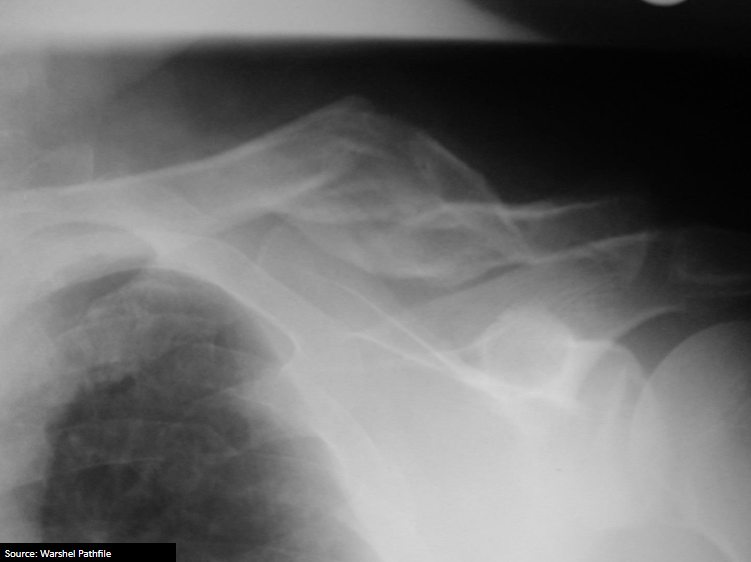

12

Q

What is the diagnosis?

What are some lesions associated with this injury?

A

Anterior shoulder dislocation

Associated with:

• Hill-Sach fracture (60%)

• Flap fracture (15%)

• Bankart lesion

• Labral tear

axillary nerve injury possible